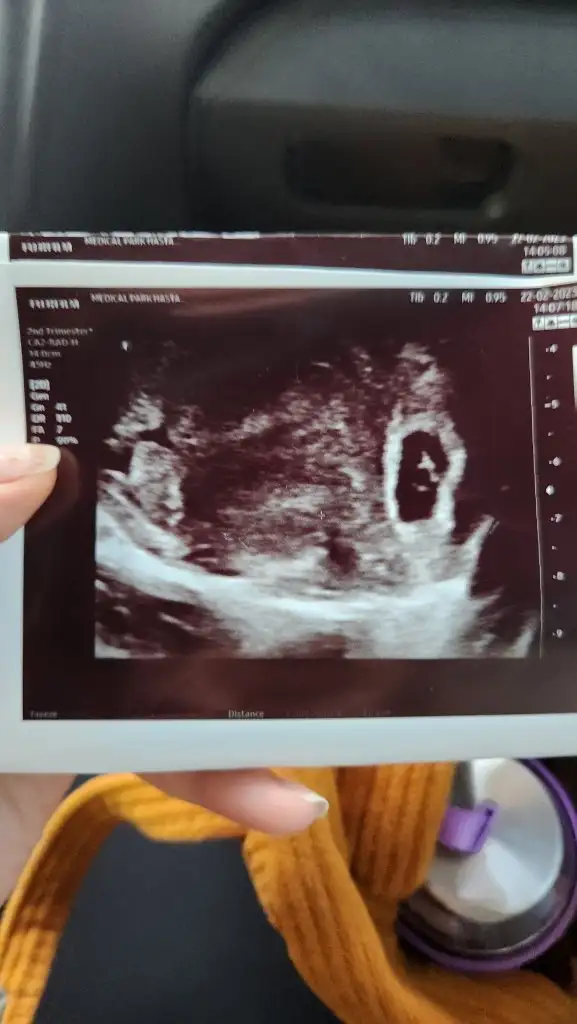

Bana da bir cinsiyet tahmininde bulunur musun 🙈 ilk fotoğraf 6+2 2. Fotoğraf 9+3

• 20230222_175000.webp

20230222_175000.webp

24,4 KB · Görüntüleme: 59